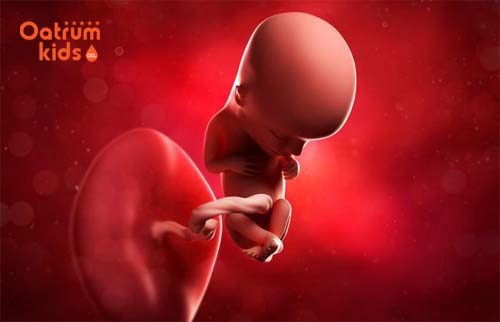

Theo các chuyên gia y tế thì khi thai được khoảng 10 tuần tuổi tức là lúc này kích thước của bé cũng đã lớn hơn trước, bé dài ra được khoảng 4cm và phát triển hầu như gần đầy đủ các bộ phận giống như của một người trưởng thành. Các mẹ có thể hình dung ra bé yêu trong giai đoạn này qua một số đặc điểm như sau:

- Lúc này bé đã biết xoè bàn tay ra rồi nắm lại thành như nắm đấm, đồng thời móng tay cũng đã hình thành rõ ở trên đầu ngón tay và đầu ngón chân.

- Trán bé cũng đã bắt đầu phồng lên hơn cùng sự phát triển của bộ não

- Một số chồi răng nhỏ cũng đang bắt đầu xuất hiện ở bên dưới nướu, thậm chí là một số xương của con yêu cũng đang cứng lại hơn.

- Các cơ quan quan trọng như não bộ, thận, gan và ruột đang bắt đầu hoạt động tốt đúng theo đúng chức năng của chúng.

- Thời điểm thai nhi 10 tuần tuổi cũng là lúc mà tủy sống của bé sản sinh ra bạch cầu, chính bạch cầu này có khả năng tạo ra kháng thể cho bé sau này.

- Cũng ở tuần thai kỳ này thì con yêu của bạn đã có thể mút ngón tay cái, bé đưa ngón tay lên miệng rồi mút, tay xoè nắm nhiều hơn.

- Lông mi của bé cũng mọc dày hơn và đầy đôi mắt giúp cho mắt bé được bảo vệ an toàn